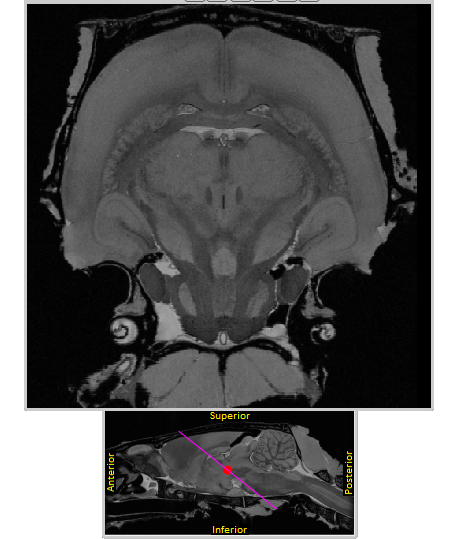

CutNII - Custom-angle slicer for brain atlas volumes

CutNII - Custom-angle slicer for brain atlas volumes Images

Description:Oblique angle cut of rat MRI (Waxholm space atlas template)